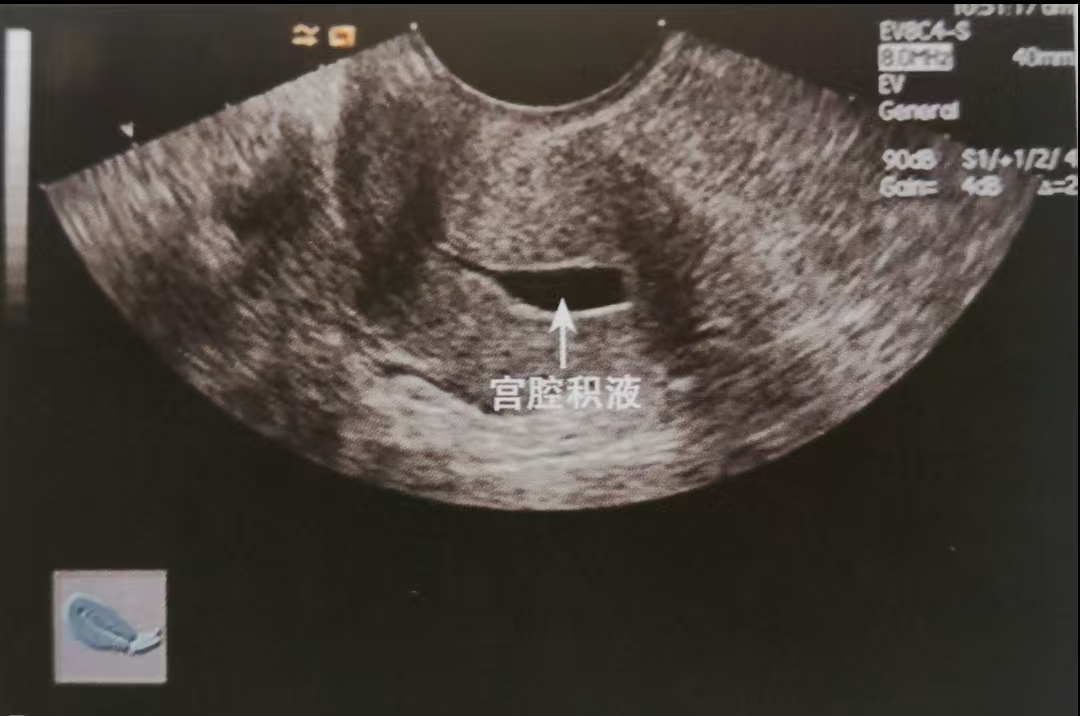

咱们先弄明白,啥是绝经后宫腔积液呢?简单来讲,就是绝经之后,子宫里积攒了一些液体。这些液体有可能是像清水一样单纯的积液,也有可能是脓液或者血液。这种情况并不算少见,大概每10个绝经后的女性朋友里,就有1 - 2个会遇到。而且啊,年纪越大越容易出现这种状况,90岁以上的女性朋友,发生率能达到26%左右呢。

经阴道超声检查:

这是最常用、也是最便宜的检查方法。它能够清楚地看到子宫里有没有积液、积液量多不多,还能查看内膜的厚度。大多数情况下,先做这个检查就足够了。